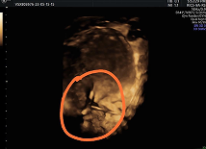

Figure 8. Shows IUCD being removed during laparoscopic surgery with a grasper

After detailed counselling, the patient consented to laparoscopic retrieval. At laparoscopy, a panoramic view revealed blood oozing from the uterine fundus with a collection in the recto-uterine space. The IUCD was visualised at the previously identified site, with one arm extruding into the peritoneal cavity. Using an atraumatic grasper, the device was gently mobilised and removed via the umbilical port without difficulty. The procedure was completed without intraoperative complications.